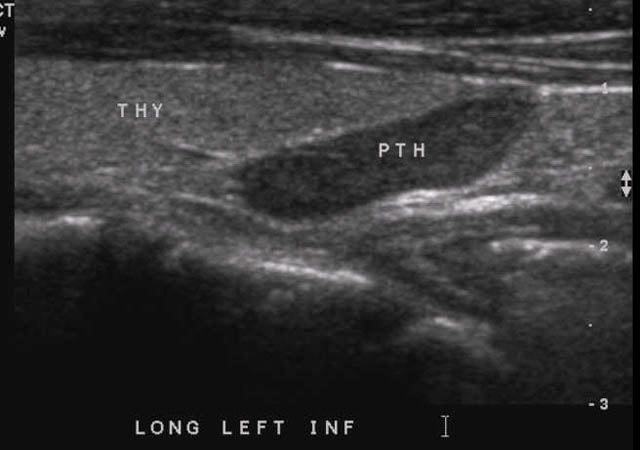

SURGICAL ENDOCRINOLOGY  Case #4 - A 60 year old with hypercalcemia    No previous image Go to next image

Ultrasound showing parathyroid adenoma